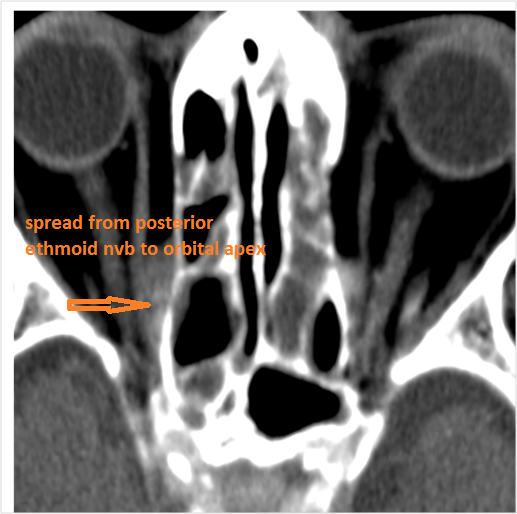

The orbital apex and the superior and inferior orbital fissures are infiltrated